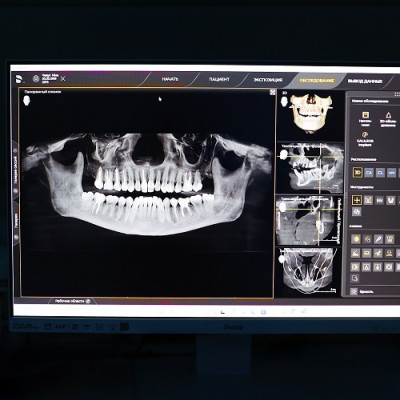

Онлайн запись на КТ